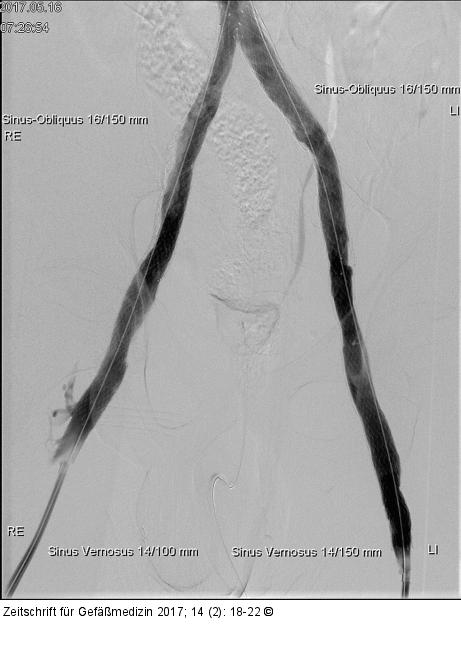

Abbildung 3: Angiographie - Stent Angiographie nach erfolgter Stentimplantation im Bereich der Beckenetage bds. sowie der infrarenalen V. cava. Die Kollateralvenen kommen bei suffizientem Abstrom über die wiedereröffneten Beckenvenen nicht mehr zur Darstellung |

Angiographie nach erfolgter Stentimplantation im Bereich der Beckenetage bds. sowie der infrarenalen V. cava. Die Kollateralvenen kommen bei suffizientem Abstrom über die wiedereröffneten Beckenvenen nicht mehr zur Darstellung |